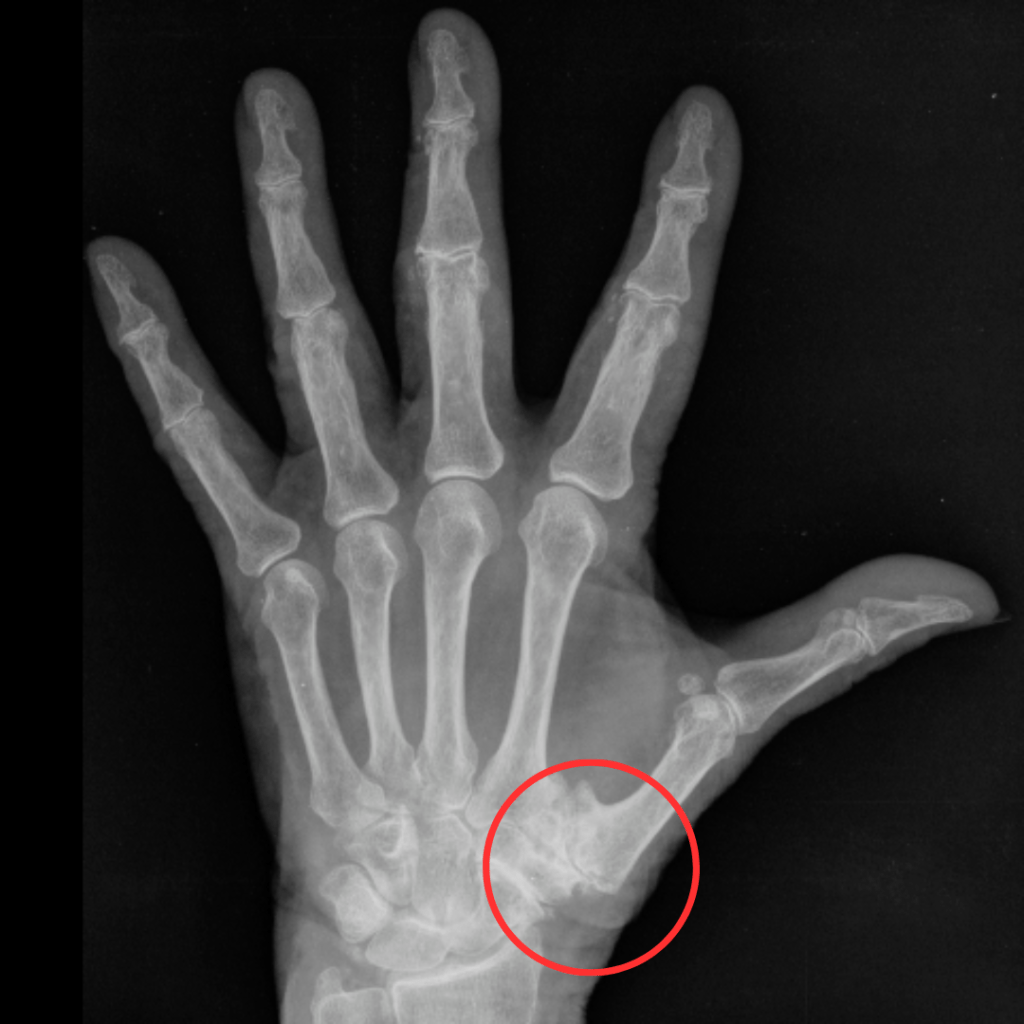

Come puoi osservare dall’immagine, la rizoartrosi è essenzialmente il risultato dell’usura della superficie articolare. Questa continua ad aggravarsi con il movimento, causando “attrito”, aumento dell’infiammazione e dolore.

“L’artrosi della base del pollice, o dell’articolazione carpometacarpale (CMC), è una delle artralgie più comuni. La rizoartrosi, nota anche come artrosi del pollice o artrosi trapeziometacarpale, è una forma di osteoartrosi che colpisce l’articolazione alla base del pollice, in particolare l’articolazione trapeziometacarpale. Questa condizione si manifesta quando il rivestimento cartilagineo dell’articolazione inizia a deteriorarsi a causa dell’usura, causando dolore, infiammazione, rigidità e una diminuzione della mobilità. La rizoartrosi è più comune nelle donne e nelle persone di età avanzata, e può essere influenzata da fattori come l’uso eccessivo, traumi ripetuti, predisposizione genetica e condizioni degenerative. Il dolore e la limitazione funzionale che ne derivano possono compromettere significativamente la capacità di eseguire attività quotidiane che richiedono l’uso del pollice. L’artrosi del pollice è spesso gestita non chirurgicamente con la modifica delle attività quotidiane, l’uso di ortesi, farmaci antinfiammatori (orali e/o topici) e iniezioni intra-articolari di corticosteroidi. Poche ricerche riportano il tasso di successo della gestione non chirurgica, ma uno studio recente di Ostergaard e colleghi ha scoperto che più del 60% dei pazienti che si sono presentati per la prima volta in una clinica di chirurgia della mano ha mostrato miglioramenti con modalità non operative. Anche Bertozzi e colleghi, in una revisione sistematica, hanno trovato che solo il 30% dei pazienti è progredito verso l’intervento chirurgico.